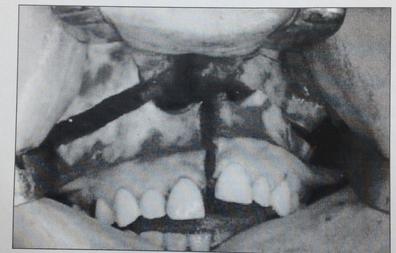

Physicians at UPMC in Pittsburgh developed new technique around 2010. Using a small endoscope, through the nose, then a small catheter through the back of the nasopharynx ( nose/mouth ) they removed ( via tiny drill ) most of C1 and C2. Quite risky being that close to brain stem. No small complications, sort of an all or nothing thing. This is me 2 weeks post surgery.